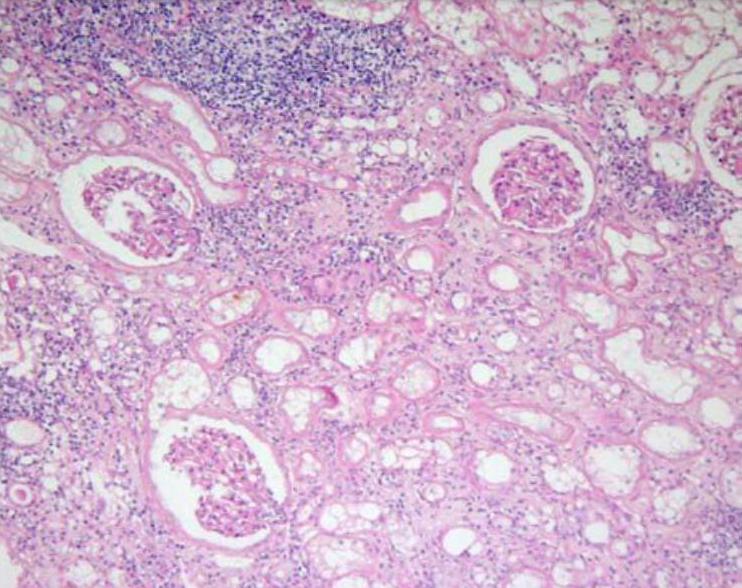

Интерстициальный нефрит (ИН) представляет собой воспалительное заболевание почек неинфекционной (абактериальной) природы с локализацией патологического процесса в межуточной (интерстициальной) ткани и поражением канальцевого аппарата нефронов. Это самостоятельная нозологическая форма заболевания. В отличие от пиелонефрита, при котором также поражаются межуточная ткань и почечные канальцы, интерстициальный нефрит не сопровождается деструктивными изменениями почечной ткани, а воспалительный процесс не распространяется на чашки и лоханки. Заболевание пока еще мало известно практическим врачам.

Клиническая диагностика интерстициального нефрита даже в специализированных учреждениях нефрологического профиля представляет большие трудности из-за отсутствия характерных, патогномоничных только для него клинических и лабораторных критериев, а также в связи со сходством его с другими формами нефропатии. Поэтому наиболее надежным и убедительным методом диагностики ИН пока является пункционная биопсия почки.